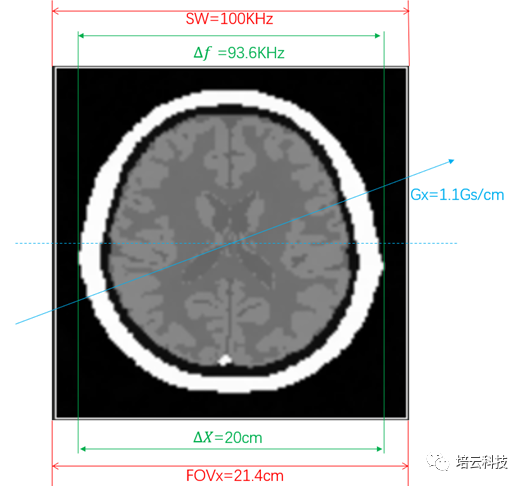

由于MRI图像是空间频率域,即空间和频率是等效的,二者之间由系数K进行转换:f=k C;f为频率,C为空间坐标位置。具体到二维平面,横向位置有fx=kxX;纵向有fy=kyY。其中,kx=𝛾Gx;ky=𝛾Gy。因此SW=100KHz的视野频率范围,在Gx=1.1Gs/cm的梯度场下,选定的视野空间范围为:FOVx=SW/𝛾Gx≈21.4cm(注1T=10000Gs)。

人脑模型的横向尺寸为20cm,在1.1Gs/cm的梯度场下,左右两侧的频率差为:Δf =𝛾GxΔX≈93.6kHz,因此脑模型图像在横向上占视野的比例约为93.6kHz/100kHz=93.6%。频率和位置映射关系如图2所示。由此也进一步说明,磁共振图像是空间频率域的信号(空间和频率一体),原始K数据是时间域的。

图2 频率编码方向的频率和位置映射关系